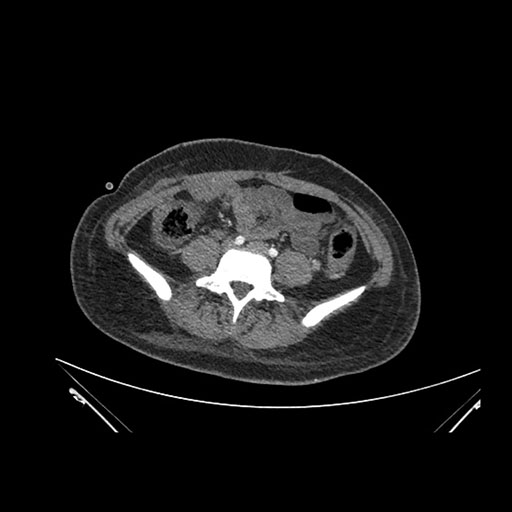

Axial Arterial

Axial Venous